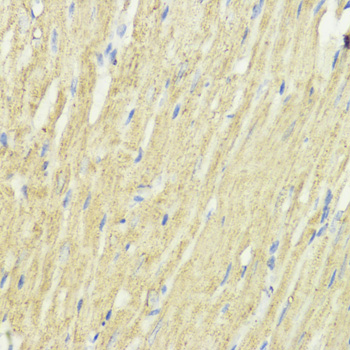

Immunohistochemistry of paraffin-embedded rat heart using EEF1A1 at dilution of 1:100 (40x lens).